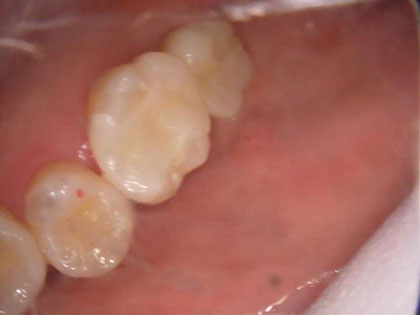

• 初診時の写真がこちら

• インプラント術前1